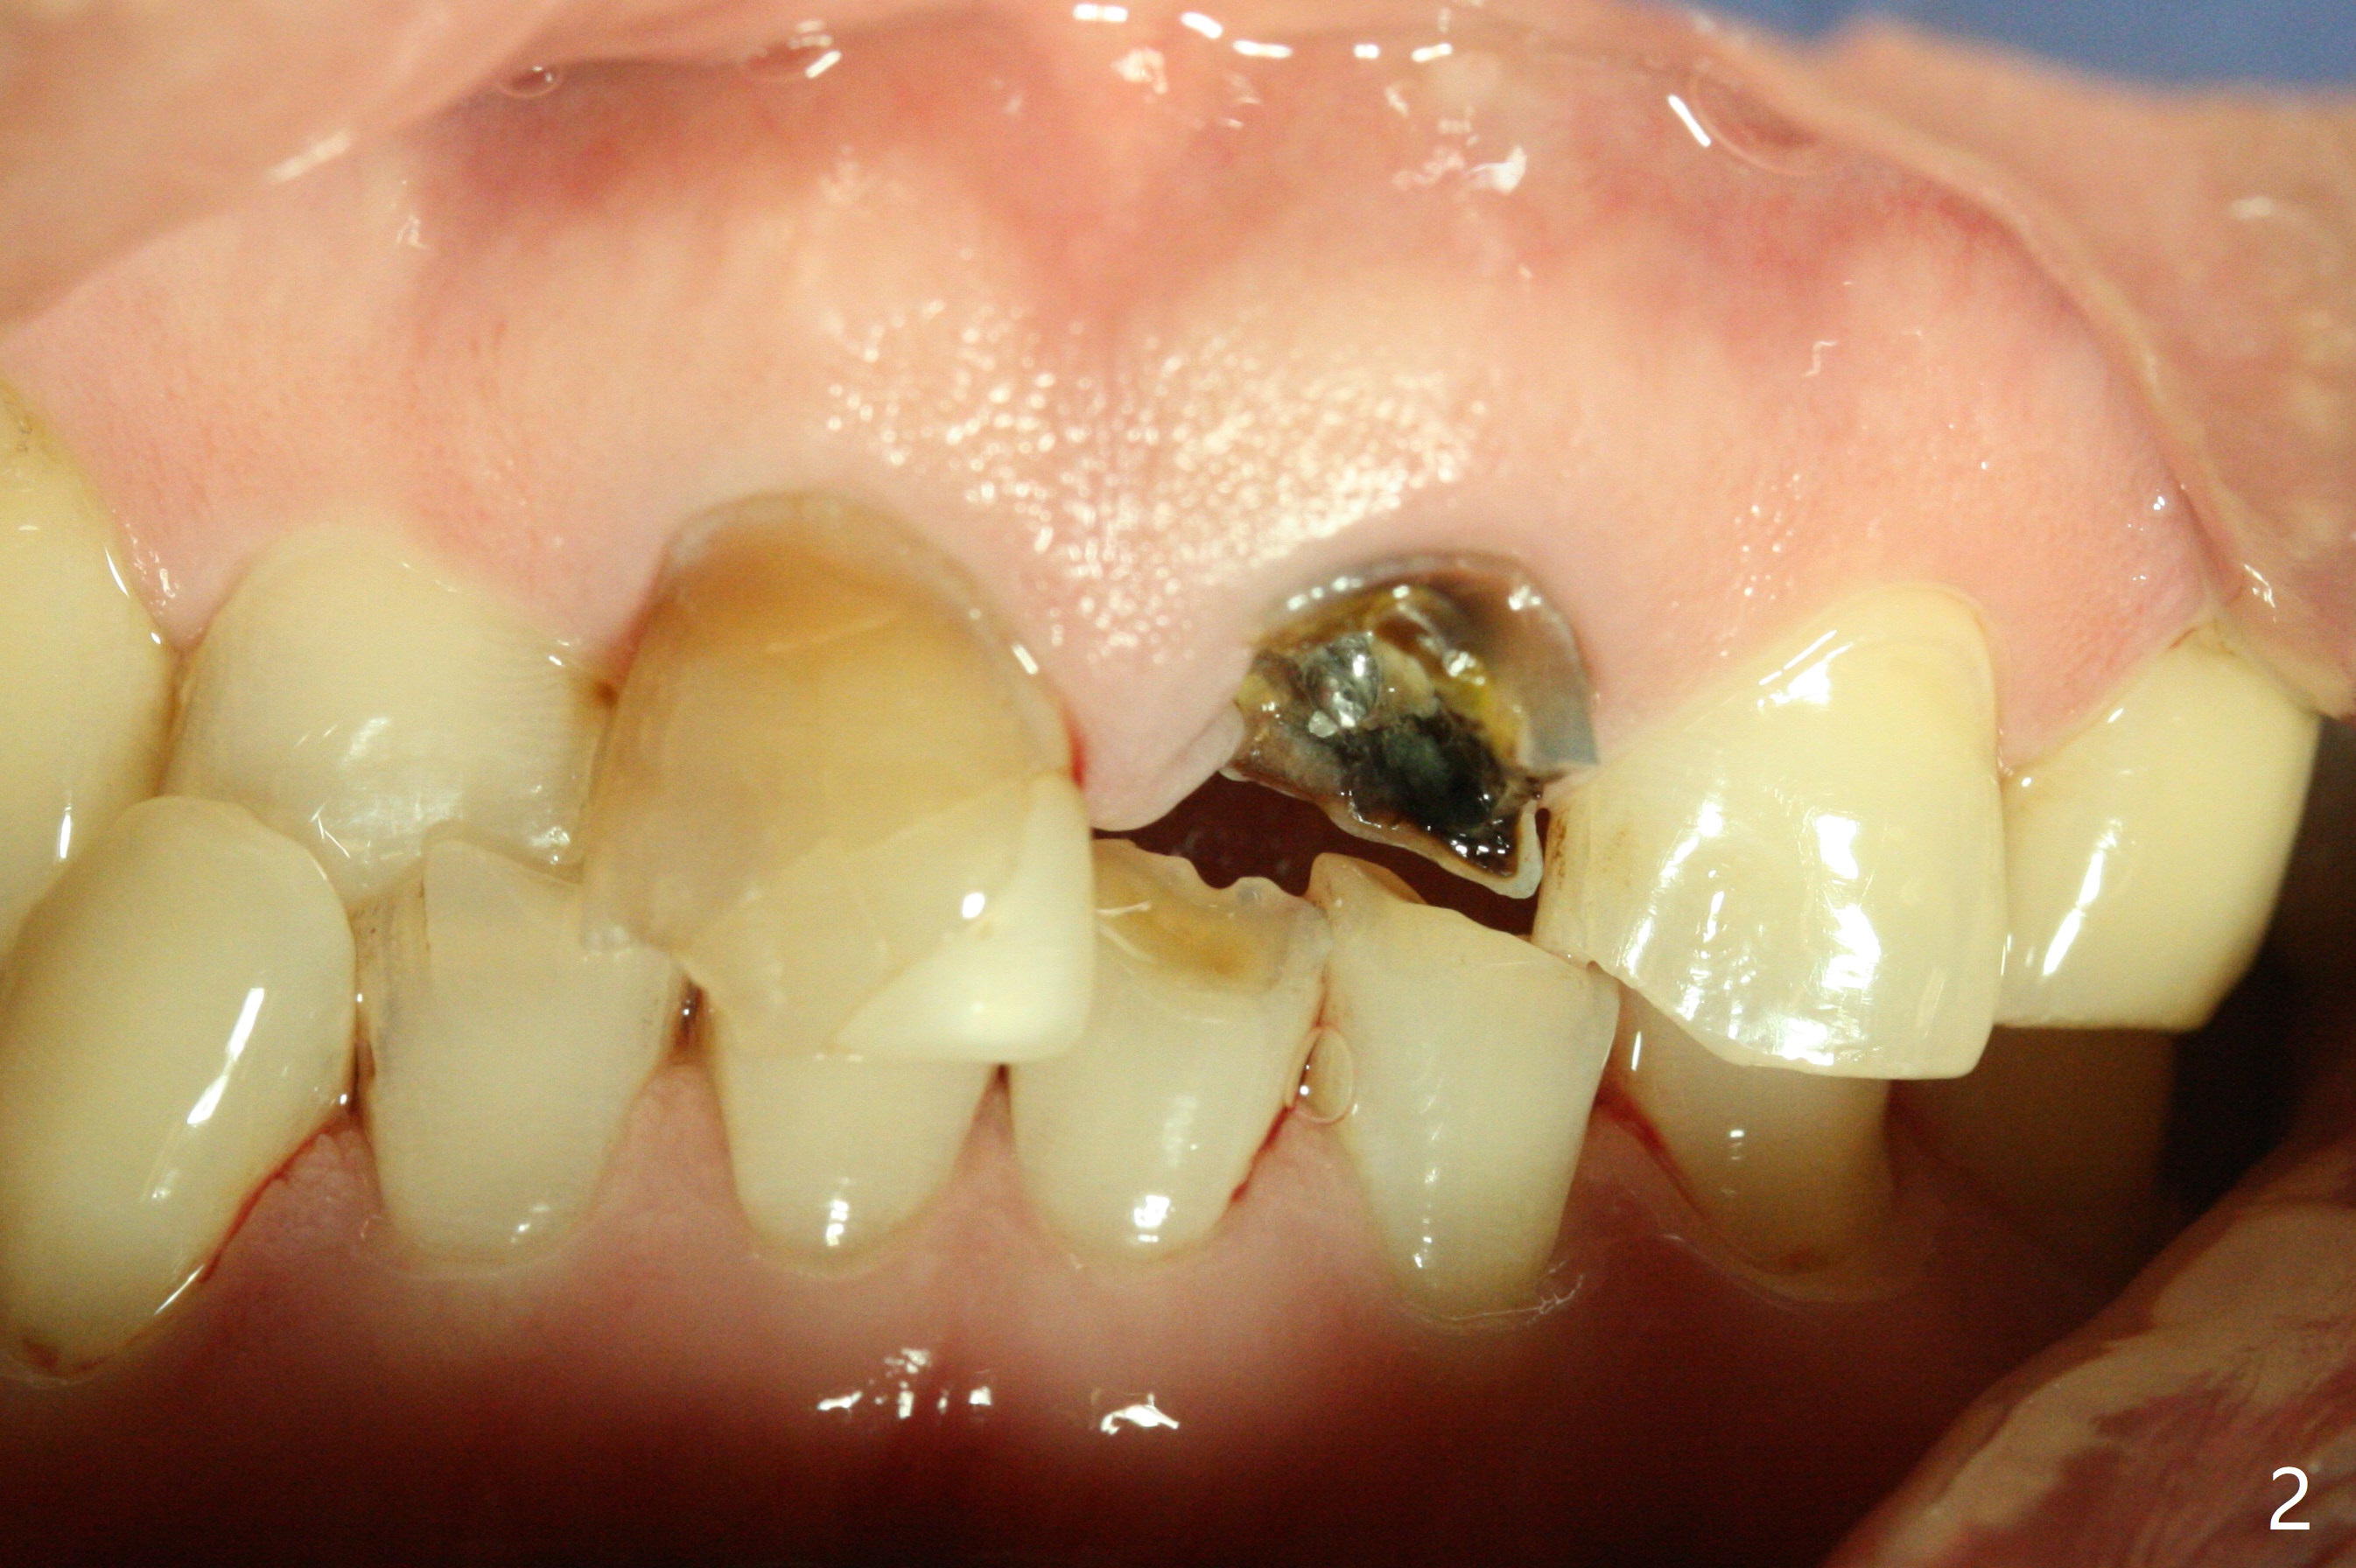

A 57-year-old man has history of fracturing post-RCT molar and difficulty in orthodontic intrusion. Now the tooth #9 fractures subgingival (Fig.1) with deep bite and heavy wear (Fig.2). A long implant will be placed to handle heavy occlusion and match the root length of the neighboring tooth (Fig.3 #10).